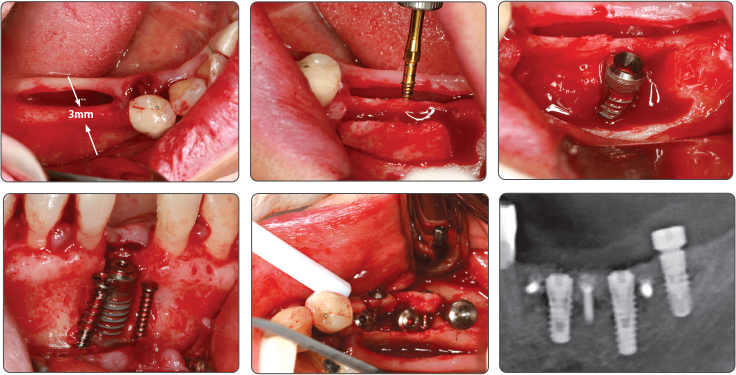

▶ Immediate Implantation and Sinus Lift Technique with Tap Drill (Ø4.0 Fixture)

2. Sinus Lift (Ø5.0 Fixture)

▶ Immediate Implantation and Sinus Lift Technique with Tap Drill (Ø5.0 Fixture)

Recommend to use Sinus Lift Drill and Spreader Drill together

1. Sinus Lift (Ø4.0 Fixture)